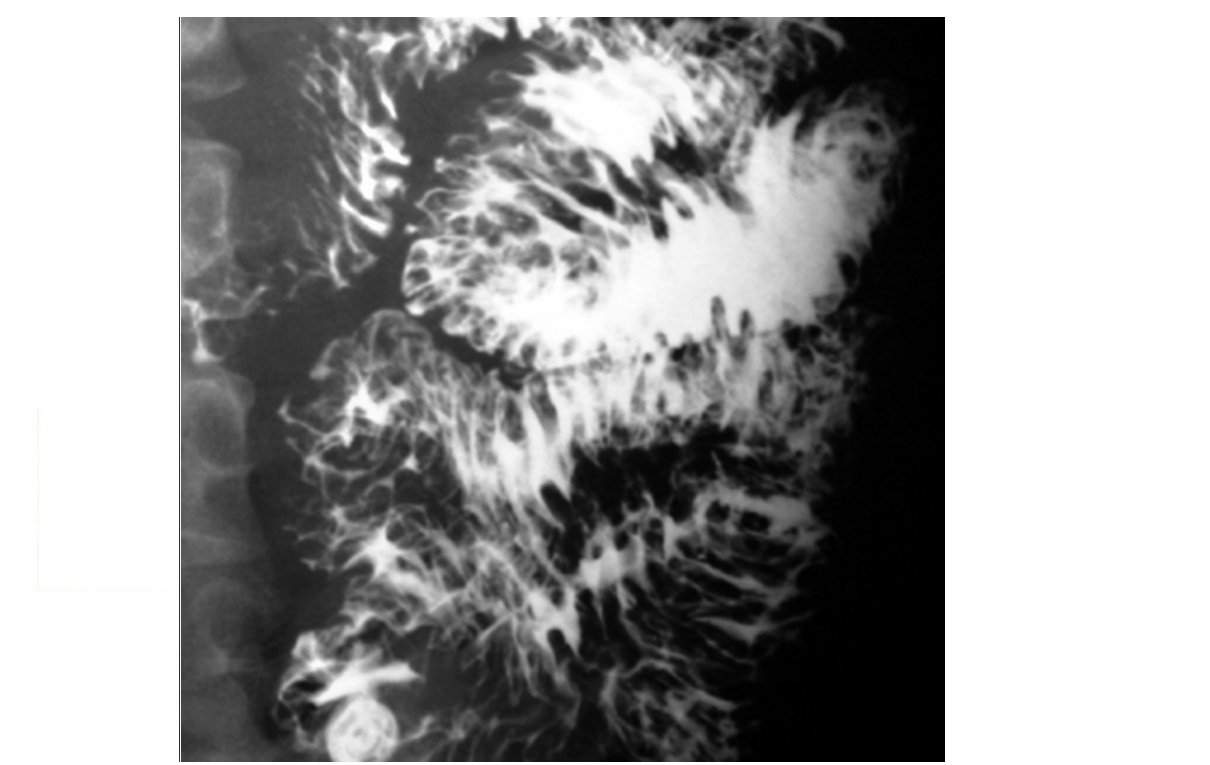

Candidiasis

irregular, longitudinal plaques with intervening normal mucosa

Typically upper 1/3 oesophagus

Immunocompromised (HIV, Transplant)

In older asymptomatic patients = Mucosal white plaques more uniform, rounded, and less well defined than candidiasis = Glycogenic Acanthosis